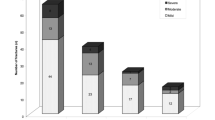

Of the 56 patients included in the study, 8 (14.3%) were men and 48 (85.7%) were women. The mean age was 72.6 ± 1.2 years. The mean follow-up for X-rays was 19 months (SD, 14.1; minimum 6, maximum 59). The fracture was spontaneous or after exertion in 6 cases (10.7%), and after falling to the ground from a standing position or lower in 50 cases (89.3%). Figure 3 shows the number of fractures identified and the vertebral endplates and walls affected. Both endplates were fractured in six cases (10.7%), and none of the endplates was involved in only one case (1.8%). Both anterior and posterior walls were fractured in 21 cases (37.5%), and none of the walls were involved in 4 cases (7.1%). Lateral wall fracture was absent in 12 cases (21.4%). At the time of initial diagnosis, 25 fractures (44.6%) showed an intravertebral cleft.